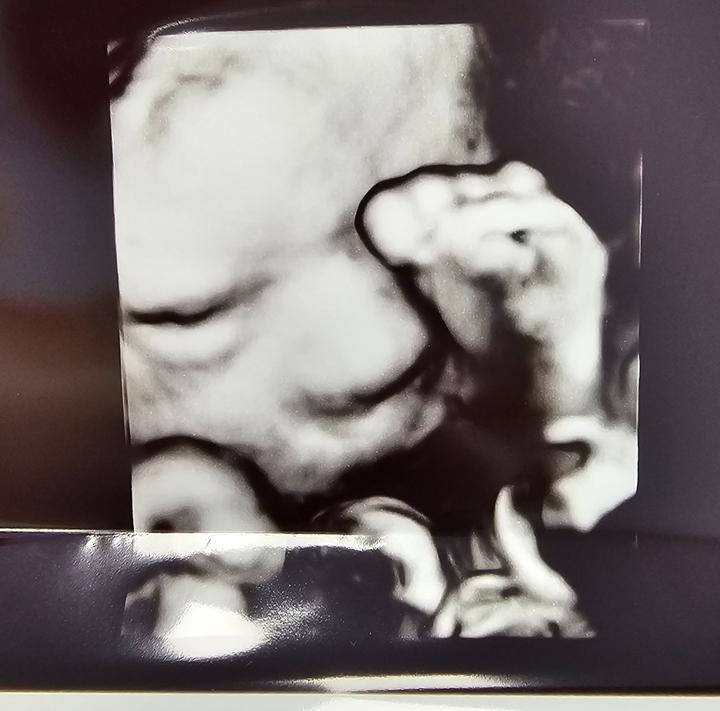

HCG synlab BA

Ahojte, akú máte skúsenosť s HCG v synlab, ako dlho ste čakali na výsledok?

Ďakujem.